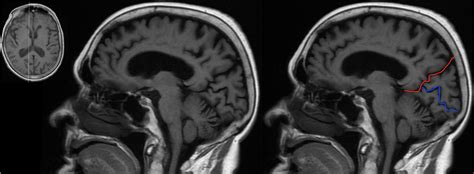

The anatomy of the human brain highlighting the Parieto Occipital Sulcus

The Parieto Occipital Sulcus is not only a random fold in the brain; it is a significant anatomical watershed that is easily identifiable on a sagittal cross-section. It commence near the top of the hemisphere, extending down and forward until it meets the calcarine sulcus, make a articulation that is vital for visual pallium orientation. This sulcus efficaciously maps out the borderline between two of the four major lobes of the brain.

• Medial Surface: It is prominently seeable on the median surface, meaning it can be best realise when the brain is catch from the midline between the two hemispheres.

• Lobular Boundary: It marks the posterior bounds of the parietal lobe and the prior limit of the occipital lobe.

• Relationship with Other Fissure: It function as a connection and boundary point for the precuneus, which consist in front of it, and the wedge, which dwell behind it.